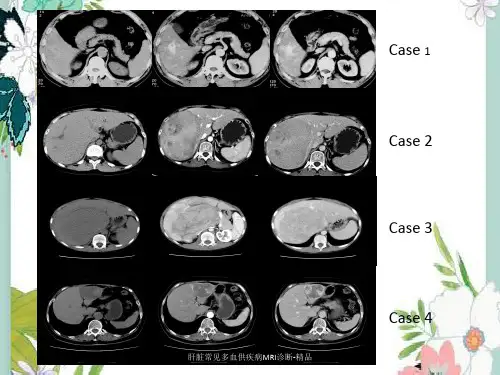

肝左叶富血供占位病变--肝左叶海绵状血管瘤病史:患者,女,43岁,因“间断后背部胀痛不适1年、体检发现肝占位1个月”入院。

图1图2图3图4CT平扫(图1):肝左叶见类圆形低密度影,边界清晰。

CT增强动脉期(图2)肝左叶病灶边缘迅速呈斑片样明显强化。

CT增强门脉期(图3)病灶强化明显,向内部填充呈结节样强化改变。

CT增强延迟期(图4)强化程度减低,仍高于周围正常肝实质,几乎完全填充病灶。

影像描述:肝左叶见类圆形低密度影,边界清晰,大小为4.0cmx2.8cm。

增强动脉期边缘斑片样明显强化,门脉期及延迟期呈向心性填充式强化,高于周围肝实质。

影像诊断:肝左叶海绵状血管瘤分析思路:1.临床病史:中年女性,体检发现,提示良性或低度恶性肿瘤。

本例为动脉期边缘斑片样明显强化,门脉期及延迟期持续呈填充式强化,强化程度明显高于周围肝实质,即为“早出晚归”强化方式,为典型海绵状血管瘤强化方式,本例符合。

肝细胞肝癌具有特征性“快进快出”的强化方式,即动脉期迅速强化,门脉期强化程度快速减低,可见假包膜形成,本例不符。

腺瘤因含有脂肪呈低密度或合并出血呈高密度,增强因完全由肝动脉供血,动脉期快速均匀强化,门脉期及延迟期强化程度逐渐减低与肝实质相同,本例不符。

最后诊断:肝左叶海绵状血管瘤。